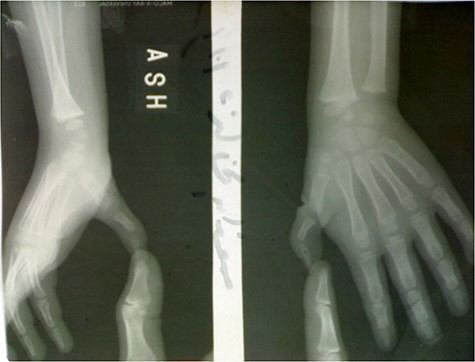

At first examination, the thumb was seen at adduction and flexion position, it cannot be extended, and after passive extension, it returns to original adduction and flexion position (Fig. 1).

There was a contracture and absence at the first web and the thumb was smaller than the opposite left one.

There was no extension in the interphalangeal joint due to the absence of EPL, also in the metacarpophalangeal joint due to the absence of EPB, whereas the CMC joint was stable.

X-ray imaging of the right hand showed small-sized bones of the right thumb including first metacarpal and phalanges, it also showed the good alignment of the CMC and MCP joints.

The following movements: flexion, adduction and opposition were within normal.

Neither stiffness nor instability in interphalangeal (IP) or metacarpophalangeal (MCP) joints was observed (Fig. 2).